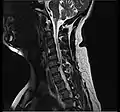

L'imagerie par résonance magnétique peut montrer la hernie, le canal vertébral, les nerfs, les tissus environnants. Les tissus mous sont les mieux analysés par cet examen qui est le plus performant pour le diagnostic de hernie discale. Les images pondérées en T2 montrent clairement la hernie.

IRM cervicale sagittale montrant une hernie discale de niveau C5-C6. IRM cervicale sagittale montrant une hernie discale de niveau C5-C6.

IRM cervicale sagittale montrant une hernie discale de niveau C6-C7. IRM cervicale sagittale montrant une hernie discale de niveau C6-C7.